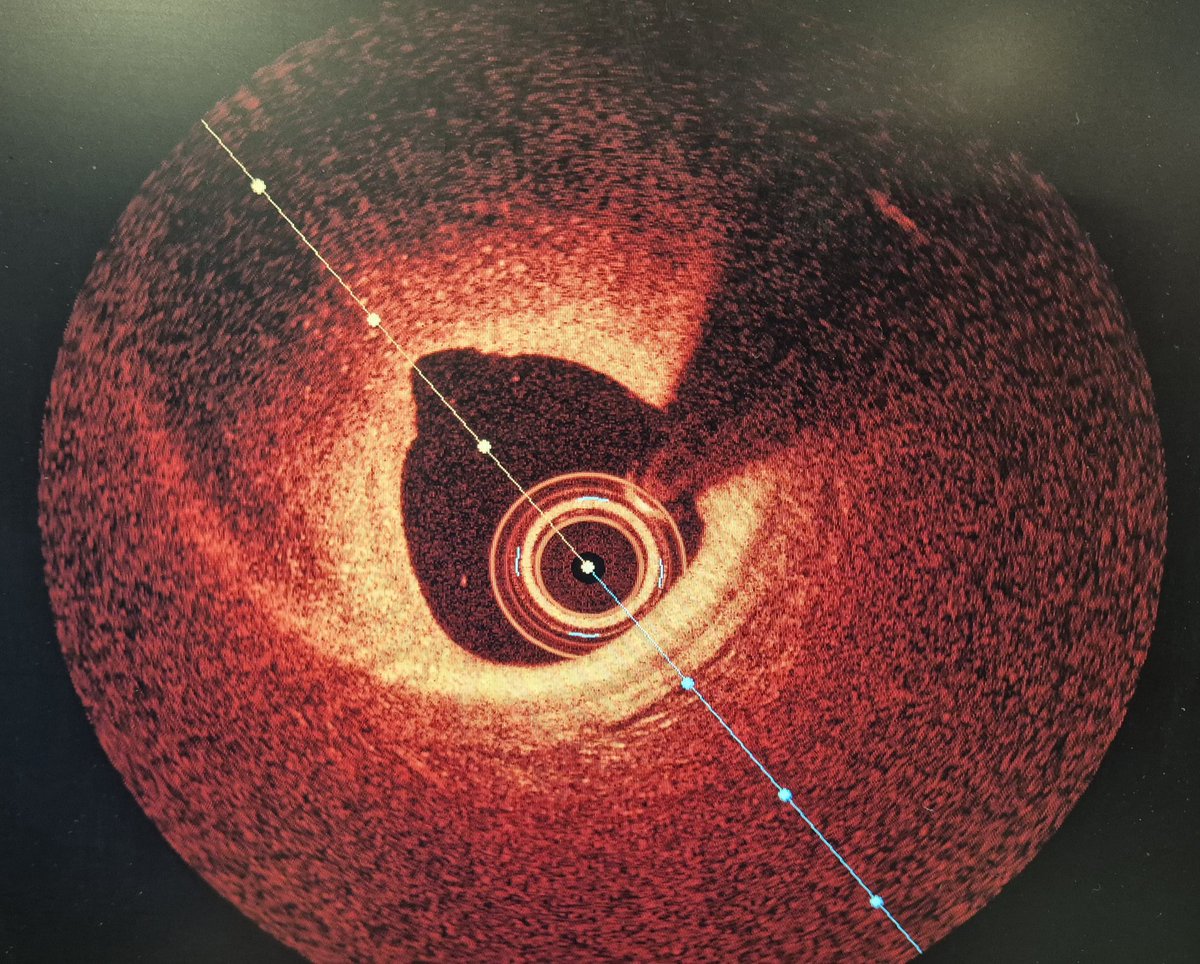

A 63 y.o female presented with NSTEMI. One year before CTA with normal LAD/RCA and mild lesion in OM1. Here is the angio and OCT images. What would you do?